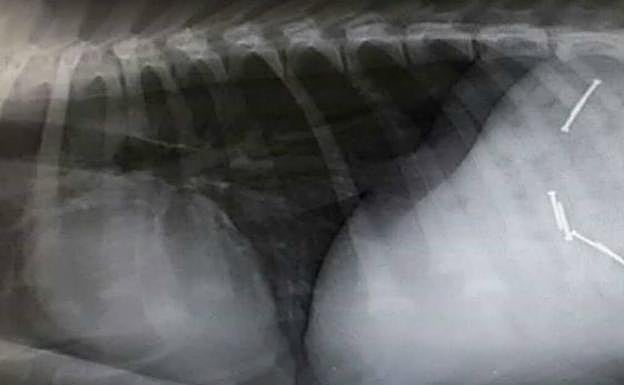

Sus propietarios tuvieron que llevarlos rápidamente al Hospital Veterinario San Vicente, donde tuvieron que ser operados de urgencia. Homer ya se recupera en casa tras recibir el alta. Por su parte, Danko, un cachorro de dos meses, también se sometió a cirugía de urgencia, pero si estado es más grave: ingirió seis clavos que le han dañado el esófago. Su pronóstico es reservado.

Más tarde se descubrió que en la citada calle había, cada pocos centímetros, trozos de salchichas con clavos de dos o tres centímetros de longitud en su interior, colocados y preparados con toda intención.